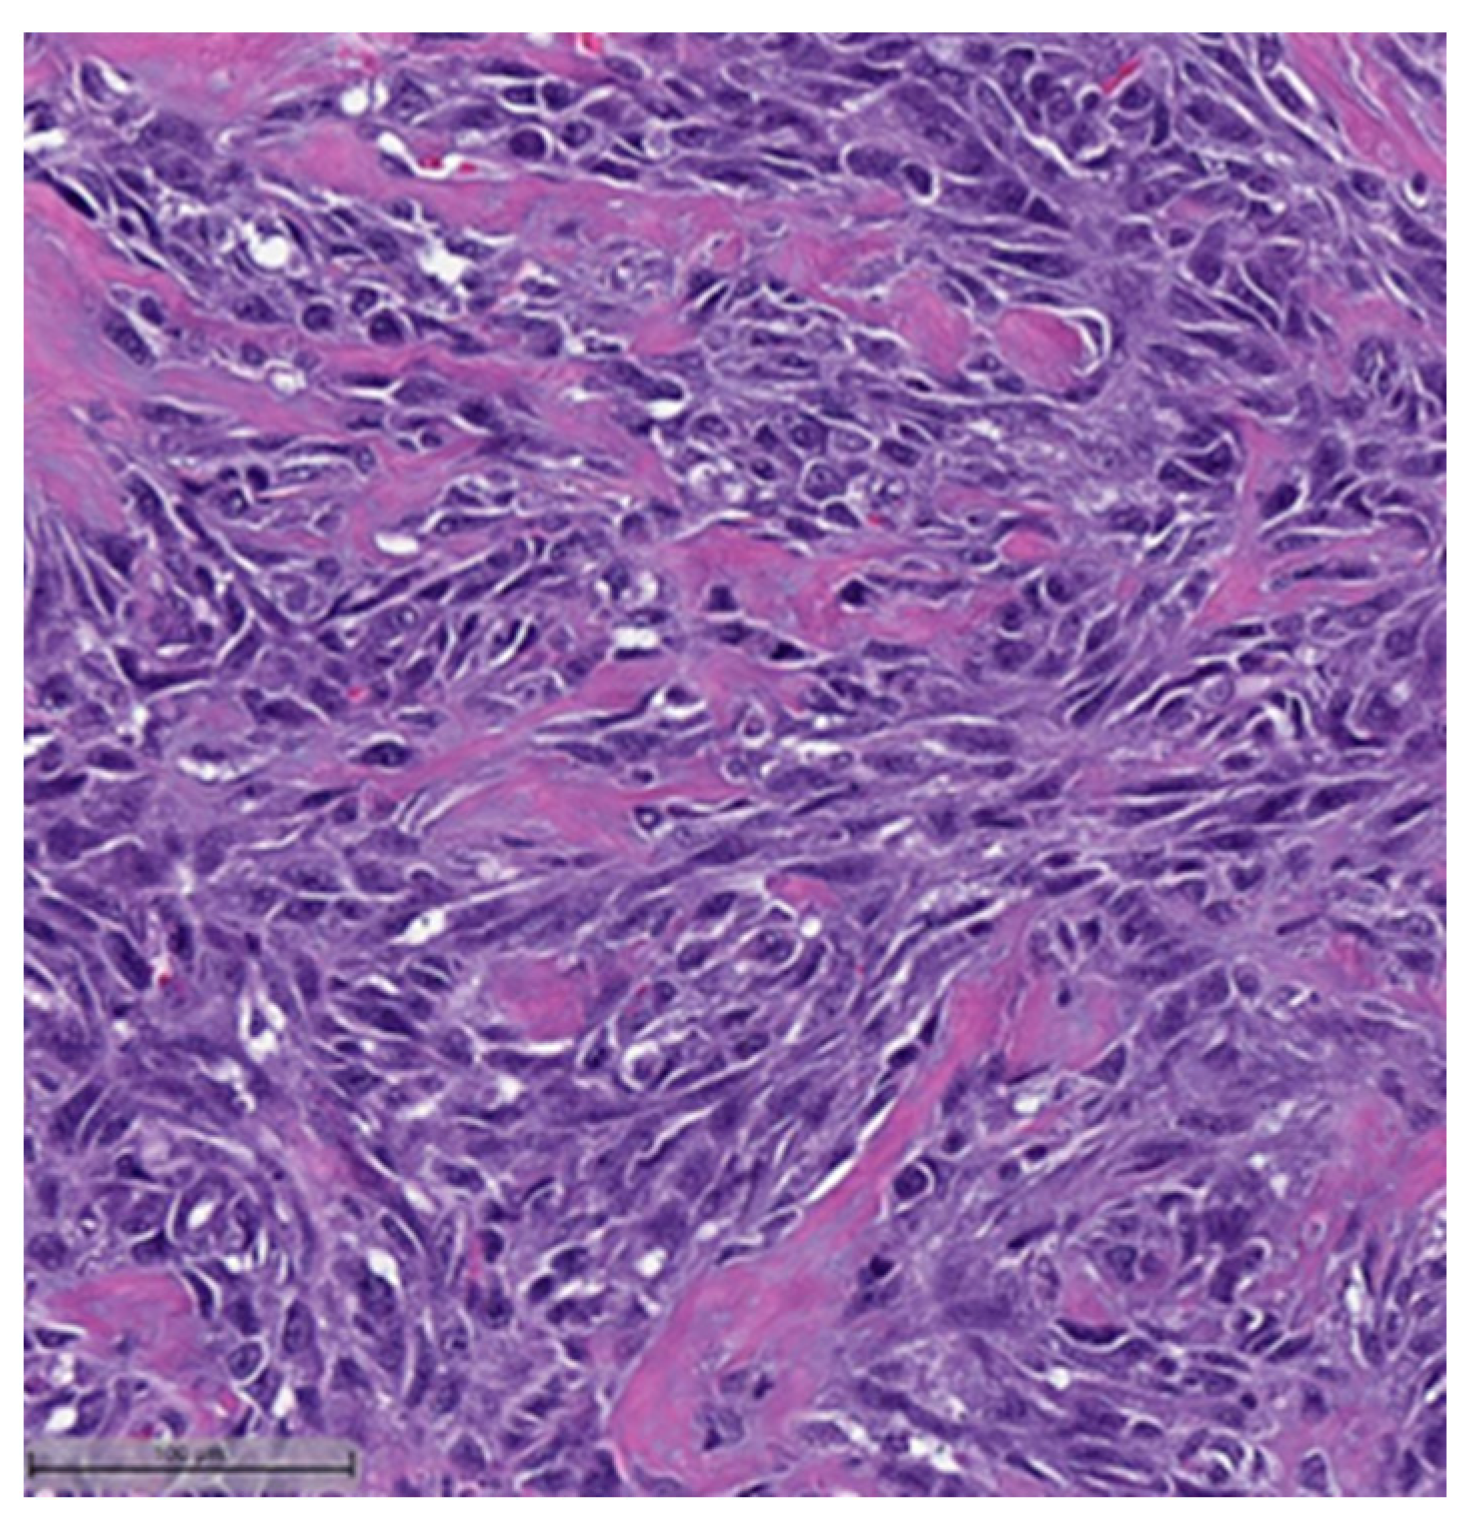

Figure 2. Squamous cell carcinoma component (H&E, 20×).- Spindle cell carcinoma (SpCC) (Figure 3);

Figure 3. Spindle cell carcinoma (H&E, 20×). - Metaplastic carcinoma with heterologous mesenchymal differentiation (MCHMD);

Spindle cell carcinoma component with pleomorphic features (H&E, 20×).